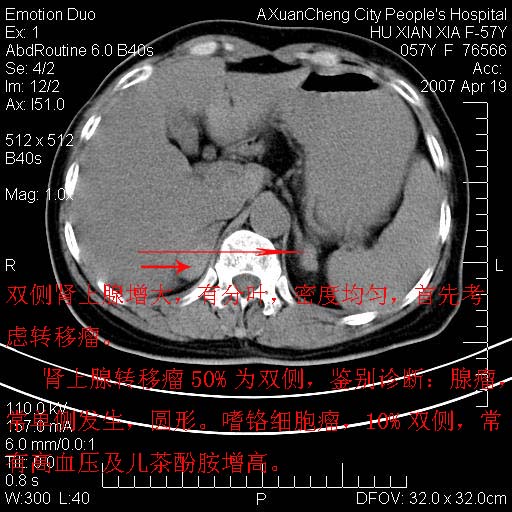

双侧肾上腺增大,有分叶,密度均匀,考虑转移建议查原发灶

1.双侧肾上腺占位,转移首先考虑。

支持肺癌肾上腺转移,肺癌患者20-30%发生肾上腺转移

双侧肾上腺结节样肿块,结合肺部肿块,考虑肺癌肾上腺转移。

双侧肾上腺及腹膜后淋巴结增大,结合胸片提示肺部占位,考虑肺癌双侧肾上腺及腹膜后淋巴结转移.